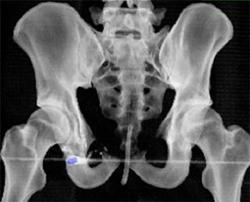

Diagnosis

Pectus Deformity